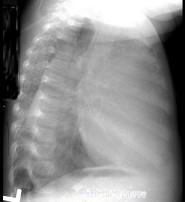

问题 12岁,女,咳嗽、咯血1个月,咳出毛发、钙化物,请结合图片,选择最可能的诊断 ( )

选项 A.肺间质纤维化 B.肺曲菌病 C.肺结核 D.畸胎瘤 E.肺癌

答案 D